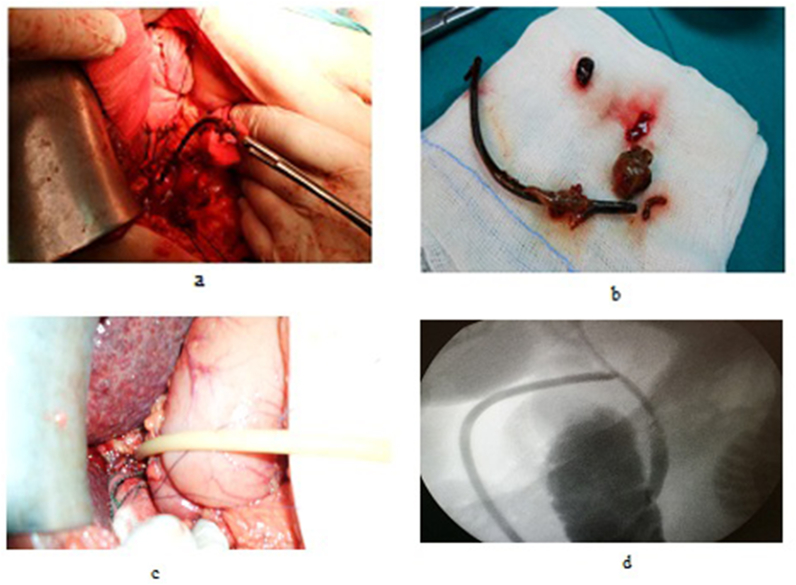

OCD: It started by open cholecystectomy (OC) and IOC through the cystic duct; then identification of CBD and the junction between the cystic duct and the CBD were done. A complete Kocher’s maneuver was performed in order to feel the retro- and intra-pancreatic portion of the CBD for easy extraction of stones and to feel the papilla. Then, two stay sutures were placed transversally at the right and left portions of the duct; then the anterior wall of the supraduodenal part of CBD was opened. The incision was performed with a sharp scalpel, then an exploration of the CBD first proximally and then distally with the Randall forceps occurred for extraction of visible stones. The proximal and distal CBD was then irrigated with saline using a soft catheter. In choledochoscopic cases, the CBD stones were entirely retrieved using choledochoscopic extraction techniques (4.5-Fr flexible choledochoscope; Karl Storz, Tuttlingen, Germany) (Fig. 5, Fig. 6). After all stones were extracted and clearance of the bile duct was confirmed; the management was as mentioned in LCD (Fig. 3, Fig. 4). Lastly, in HJ cases, the biliary-enteric anastomosis was done by 4.0 PDS sutures (posterior continuous and anterior interrupted sutures) [ref. 20].

TDS (for impacted stones in the ampulla of Vater): A Kocher maneuver was performed, after which a longitudinal anterior duodenotomy was made at the level of the ampulla, the ampulla and distal CBD were divided for a distance of 1.5–2 cm, directed anteromedially. The sphincter was divided sequentially between small clamps, with sequential suture approximation of the duodenal and bile duct mucosa using fine interrupted absorbable suture 4.0 vicryle. The duodenum was then closed transversely [ref. 8,ref. 33].